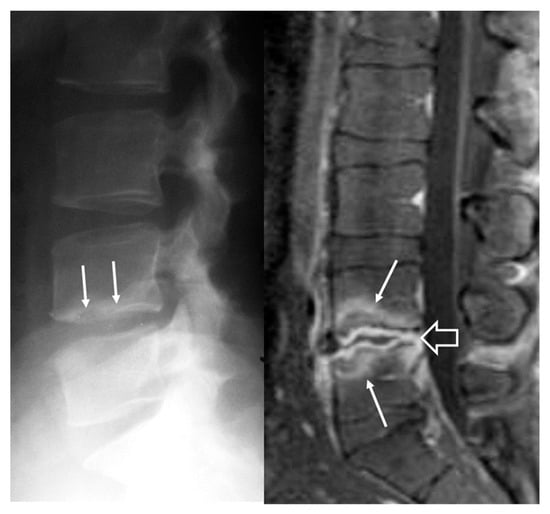

- Bozgeyik, Z.; Ozdemir, H.; Demirdag, K.; Ozden, M.; Sonmezgoz, F.; Ozgocmen, S. Clinical and MRI findings of brucellar spondylodiscitis. Eur. J. Radiol. 2008, 67, 153–158. [Google Scholar] [CrossRef]

- Bozgeyik, Z.; Aglamis, S.; Bozdag, P.G.; Denk, A. Magnetic resonance imaging findings of musculoskeletal brucellosis. Clin. Imaging 2014, 38, 719–723. [Google Scholar] [CrossRef]

- Ozaksoy, D.; Yucesoy, K.; Yucesoy, M.; Kovanlikaya, I.; Yuce, A.; Naderi, S. Brucellar spondylitis: MRI findings. Eur. Spine J. 2001, 10, 529–533. [Google Scholar] [CrossRef] [PubMed]

- Harman, M.; Unal, O.; Onbasi, K.T.; Kiymaz, N.; Arslan, H. Brucellar spondylodiscitis: MRI diagnosis. Clin. Imaging 2001, 25, 421–427. [Google Scholar] [CrossRef] [PubMed]

- Chelli Bouaziz, M.; Ladeb, M.F.; Chakroun, M.; Chaabane, S. Spinal brucellosis: A review. Skelet. Radiol. 2008, 37, 785–790. [Google Scholar] [CrossRef]

- Raptopoulou, A.; Karantanas, A.H.; Poumboulidis, K.; Grollios, G.; Raptopoulou-Gigi, M.; Garyfallos, A. Brucellar spondylodiscitis: Noncontiguous multifocal involvement of the cervical, thoracic, and lumbar spine. Clin. Imaging 2006, 30, 214–217. [Google Scholar] [CrossRef] [PubMed]

- Sharif, H.S.; Clark, D.C.; Aabed, M.Y.; Haddad, M.C.; al Deeb, S.M.; Yaqub, B.; al Moutaery, K.R. Granulomatous spinal infections: MR imaging. Radiology 1990, 177, 101–107. [Google Scholar] [CrossRef]

- al-Shahed, M.S.; Sharif, H.S.; Haddad, M.C.; Aabed, M.Y.; Sammak, B.M.; Mutairi, M.A. Imaging features of musculoskeletal brucellosis. Radiographics 1994, 14, 333–348. [Google Scholar] [CrossRef]

- Guo, H.; Lan, S.; He, Y.; Tiheiran, M.; Liu, W. Differentiating brucella spondylitis from tuberculous spondylitis by the conventional MRI and MR T2 mapping: A prospective study. Eur. J. Med. Res. 2021, 26, 125. [Google Scholar] [CrossRef]

- Li, W.; Zhao, Y.H.; Liu, J.; Duan, Y.W.; Gao, M.; Lu, Y.T.; Yao, L.; Li, S.L. Imaging diagnosis of brucella spondylitis and tuberculous spondylitis. Zhonghua Yi Xue Za Zhi 2018, 98, 2341–2345. [Google Scholar] [CrossRef]